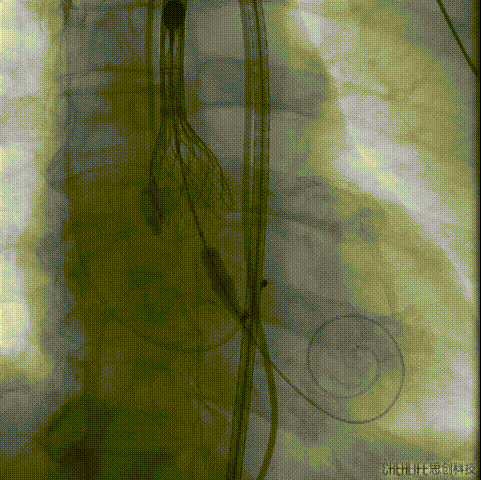

根部造影

定位

第一次释放

第一次释放定位过高

回收

第二次释放

释放至可回收极限

术后